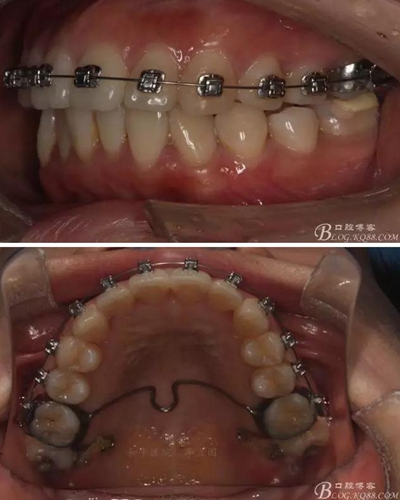

患者,女,主訴:牙齒不齊。

如圖,該病例為簡單排齊病例,但77鎖合是矯治中的關(guān)鍵所在,你會怎么處理?

該病例主要為17、27頰側(cè)位同時伴有伸長,當(dāng)然種植支抗可以解決,但還有簡單實用的辦法嗎?如圖,在橫腭桿遠中延伸出牽引鉤,位置盡量遠離合平面,7粘舌側(cè)扣,牽引力的方向為壓低及舌向,下圖為兩個月的效果,17已到位,27還未到位。